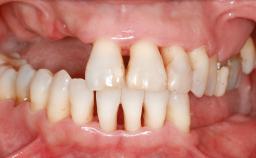

A 47-year-old Caucasian woman with a single-tooth edentulous space at the site of the left maxillary canine was referred for treatment. She had undergone traumatic extraction of this impacted canine several months before referral. Her chief complaint was the dissatisfying appearance of her smile. The patient desired a stable and esthetic rehabilitation of the site. Her dental history showed no evidence of periodontal disease or bruxism. She had no systemic diseases, was not taking any medications, and did not smoke. The extraoral examination revealed a high lip line and an inadequate soft-tissue volume at the defective canine site. Large black triangles were visible between the canine and its adjacent teeth.

Lip Line No exposure of papillae Exposure of papillae Full exposure of mucosa margin

Soft Tissue Anatomy Intact Defective